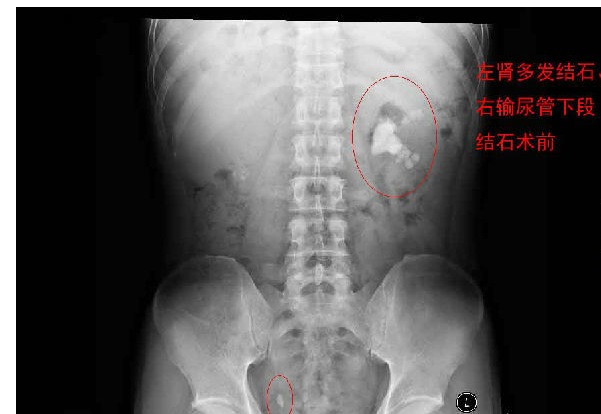

在手術(shù)室一個(gè)角落里總是傳來(lái)“嘟嘟、砰砰……”的打擊聲,第一次進(jìn)去的人總是忍不住要前往12手術(shù)間看個(gè)究竟。其實(shí)這就是三院泌尿外科微創(chuàng)手術(shù)間,也就是專治微創(chuàng)內(nèi)鏡下碎腎結(jié)石、泌尿結(jié)石、膀胱結(jié)石、前列腺電切……

你在這里總是能看到被一堆儀器圍繞著的醫(yī)生努力砰擊著各類頑固石頭,為什么說(shuō)是頑固的石頭呢?因?yàn)槌死^發(fā)性的找到原因,去除原因之后可以不再?gòu)?fù)發(fā)以外,大部分結(jié)石還是經(jīng)常復(fù)發(fā)的。所以需要患者平時(shí)注意預(yù)防。

每天早上手術(shù)間響起泌外醫(yī)生們特有的交談聲音和機(jī)器們互相的運(yùn)轉(zhuǎn)聲交替成了一道熟悉不變的旋律,從手術(shù)室護(hù)士擺著各種專用體位,推著各種器械,液體進(jìn)進(jìn)出出,醫(yī)生們應(yīng)用著各種碎石手段消滅石頭,利用氣壓彈道、激光、超聲等碎石工具,把結(jié)石擊碎取出,一陣忙碌的節(jié)奏。泌尿外科的手術(shù)時(shí)間都不長(zhǎng),每天手術(shù)例數(shù)又多,你就會(huì)看見(jiàn)這么一群人來(lái)來(lái)回回,醫(yī)生護(hù)士還是那么個(gè),病人都換了無(wú)數(shù)。最長(zhǎng)一次從早上8點(diǎn)到隔天凌晨2點(diǎn)才結(jié)束手術(shù),回到家就立馬睡覺(jué)都顧不上吃飯?,F(xiàn)在手術(shù)間正做著一臺(tái)經(jīng)皮腎鏡下碎石取石術(shù),這是我們醫(yī)院泌外科的王牌。

經(jīng)皮腎鏡取石術(shù),就是在腰部建立一條從皮膚到腎臟的通道,通過(guò)這個(gè)通道把腎鏡插入腎臟,英文簡(jiǎn)寫為PCNL。經(jīng)皮腎鏡取石術(shù)是腎結(jié)石治療的現(xiàn)代微創(chuàng)技術(shù),我院在惠州率先開(kāi)展此項(xiàng)技術(shù),現(xiàn)在每年進(jìn)行數(shù)百例手術(shù),基本上已經(jīng)淘汰了開(kāi)放手術(shù)取石。經(jīng)皮腎鏡取石術(shù)是一項(xiàng)技術(shù)性非常強(qiáng)的手術(shù)。我們知道,腎臟是血管非常豐富的器官,腎臟血流占心臟排出血量的1/4。既要盡量避免出血、又要努力取凈結(jié)石、還要保護(hù)腎臟功能,這需要非常精細(xì)的手術(shù)技術(shù)。從某種程度上說(shuō),這個(gè)手術(shù)要比治療腎癌的腎切除術(shù)難度大很多。傳統(tǒng)的“開(kāi)刀取石”的方法,需要在腰部做一個(gè)的大切口,切開(kāi)腰部的肌肉,把腎臟分離出來(lái),在腎盂或腎實(shí)質(zhì)切開(kāi)一個(gè)小口,將結(jié)石取出來(lái)。這種方法損傷大、出血較多、痛苦重、恢復(fù)慢。通常手術(shù)后需要住院7天以上。因?yàn)槭中g(shù)切口大,不但皮膚不美觀,而且手術(shù)后患者的體力受影響比較大。與開(kāi)放手術(shù)相比,經(jīng)皮腎鏡取石術(shù)具有損傷小、痛苦輕、取石徹底、恢復(fù)快等優(yōu)點(diǎn)。腰部的切口通常小,因?yàn)椴磺虚_(kāi)肌肉,不但不影響美觀,而且手術(shù)后對(duì)勞動(dòng)力幾乎沒(méi)有影響。手術(shù)后住院時(shí)間也明顯縮短。與腹腔鏡取石相比,經(jīng)皮腎鏡取石術(shù)對(duì)腎臟及周圍的結(jié)構(gòu)影響小,不影響以后的各種腎臟手術(shù)。與體外碎石相比,它的治療周期短、效果立竿見(jiàn)影,對(duì)腎功能的影響也較小。(手術(shù)室/麻醉科 阮伊莎)